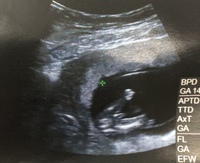

妊娠4ヶ月 妊娠12週 13週 14週 15週 妊娠初期 の超音波写真 妊娠 出産 育児に関する総合情報サイト ベビカム

妊娠14週のエコーです の辺りが性器だと思うのですが性別は Yahoo 知恵袋

エコー写真についてです先日14週の検診でした へその緒なのか シンボルなのか先 Yahoo 知恵袋